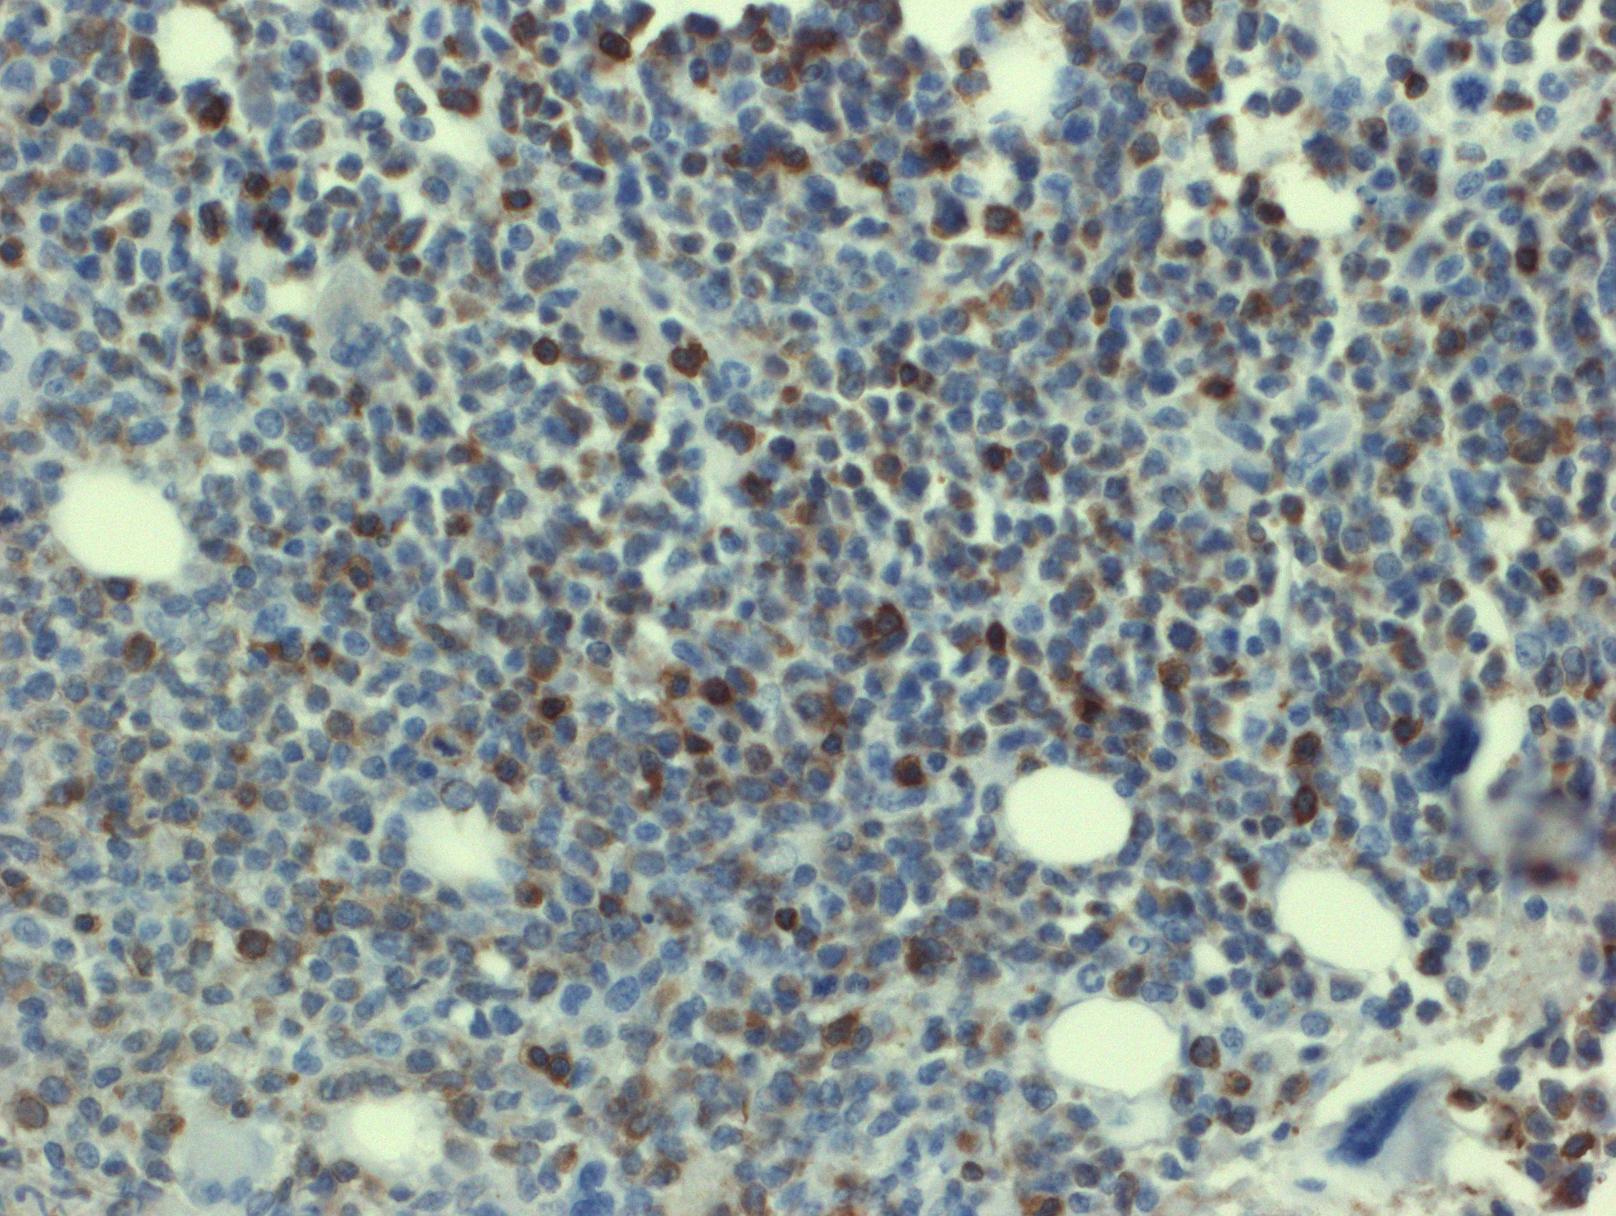

- 免疫表型: T-ALL/LBL 中淋巴母细胞呈 TdT 阳性,可表达 CD1a、CD2. CD3. CD4. CD5. CD7 和 CD8 中的一种或多种,最常见的是 CD7 和胞浆 CD3ε 阳性表达,其中只有 CD3 具有确定肿瘤细胞来源的特异性。CD4 和 CD8 常有合表达,CD10 也可以阳性;但这些都不具特异性。不成熟抗原除 TdT、CD1a、CD34 外,CD99 的表达也可表明其前体细胞的特性。部分病例表达 TAL1(核染)。偶有病例 CD117 阳性(常伴有 FLT3 突变)。10%病例表达 CD79a,少数可以表达 CD13 和/或 CD33。根据分化阶段不同,可将 T-ALL 分为以下几型:原 T(Pro-T):cCD3+、CD7+、CD2-、CD1a-、CD34-/+、CD4-、CD8-;前 T (Pre-T):cCD3+、CD7+、CD2+、CD1a-、CD34+/-、CD4-、CD8-;皮质 T(cortical T):cCD3+、CD7+、CD2+、CD1a +、CD34-、CD4+、CD8+;髓质 T(medullary T):cCD3+、CD7+、CD2+、CD1a-、CD34-、sCD3+、CD4 或 CD8 阳性。前两型中的很多病例符合 WHO 2017 年版分类中的早期前 T 淋巴母细胞白血病 (见下)。